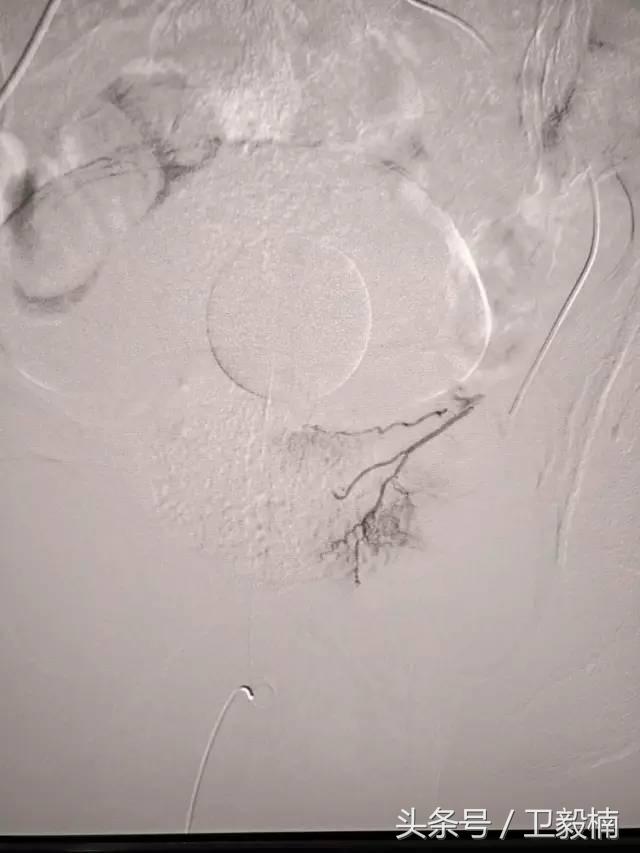

五、出血性疾病:鼻腔大出血、咯血、上消化道大出血、经皮肾镜术后出血、膀胱出血、产后出血等

2、经导管血管栓塞法(Transcatheter embolization)

经原血管造影的导管或特制的导管,将栓塞物送至靶血管内,一是治疗内出血如外伤性脏器出血、溃疡病、肿瘤或原因未明的脏器出血。另一是用栓塞法治疗肿瘤,因肿瘤循环部分或全部被栓塞物阻断,以达控制肿瘤之生长,或作为手术切除的一种治疗手段;亦可用于非手术脏器切除,例如注射栓塞物质于脾动脉分支内,即部分性脾栓塞,以治疗脾功亢进,同时不影响脾脏的免疫功能。

常用的栓塞物质如自体血凝块、明胶海绵、无水酒精、聚乙烯醇、液体硅酮、不锈钢圈、金属或塑料小球及中药白芨等。